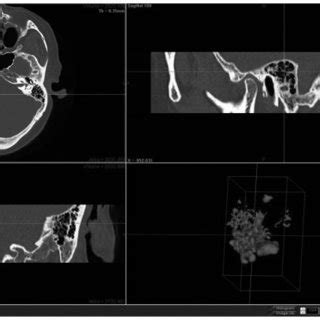

In addition to the information above, here is a curated collection of images related to Computerized Tomographs A And Three Dimensional Reconstruction B Of.

- (a) Simulated 3d Tomographic Reconstruction. 3d Reconstruction Using ...